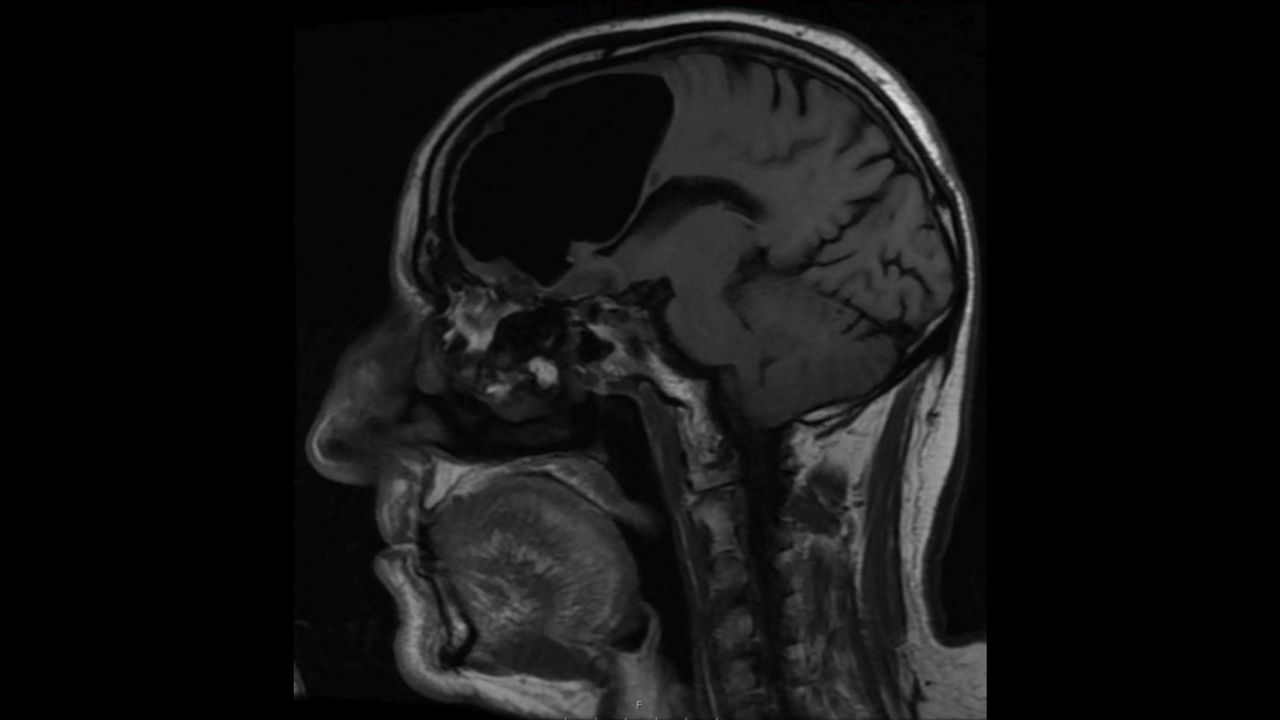

Air Pocket In Brain . — he had a 9 cm pocket of air in the right frontal lobe of his brain. — cerebral air embolism (cae) is a serious disease, often underdiagnosed due to nonspecific neurological findings and. Used a bioluminescent oxygen indicator to examine oxygen partial pressure in different parts of the mouse brain at high spatial and temporal resolution. — cnn — doctors treating a patient who had complained of repeatedly losing his balance made an unexpected. — pneumocephalus, also known as pneumatocele. The recognition of this finding can at first blush be. — intracranial gas is commonly detected on neuroimaging. — however, our understanding of the dynamics of brain tissue oxygen tension during physiological conditions is still limited. An mri confirmed the presence of this.

— he had a 9 cm pocket of air in the right frontal lobe of his brain. — cnn — doctors treating a patient who had complained of repeatedly losing his balance made an unexpected. — however, our understanding of the dynamics of brain tissue oxygen tension during physiological conditions is still limited. — cerebral air embolism (cae) is a serious disease, often underdiagnosed due to nonspecific neurological findings and. An mri confirmed the presence of this. The recognition of this finding can at first blush be. — intracranial gas is commonly detected on neuroimaging. — pneumocephalus, also known as pneumatocele. Used a bioluminescent oxygen indicator to examine oxygen partial pressure in different parts of the mouse brain at high spatial and temporal resolution.